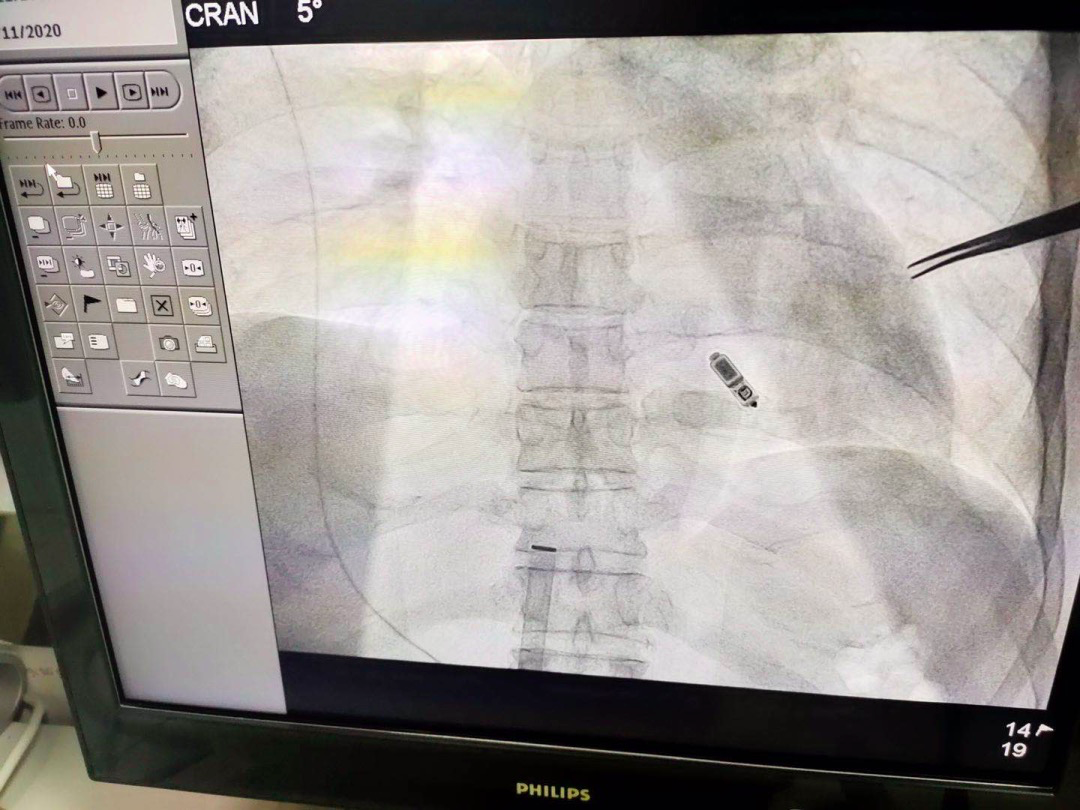

9月11日下午,在介入专家团队的密切配合下,广医五院心血管内科专家团队运用娴熟的技术,通过股静脉穿刺,将无导线起搏器植入到李叔的右心室。手术十分顺利,仅仅用时47分钟,就为他成功安装了无导线起搏器。植入后,李叔几乎感觉不到起搏器的存在,也未发生任何并发症。

无导线起搏器顾名思义,就是没有导线的起搏器。它如胶囊大小,重量仅2g左右,电池寿命超过10年以上,拥有兼容核磁共振扫描等创新功能。

与传统心脏起搏器相比,体积和重量仅为传统起搏器的十分之一,是重量最轻、体积最小的一种起搏器。它经穿刺血管,直接放入心腔内膜,无需植入心内膜导线,也无需在胸前皮下制作囊袋放置脉冲发生器,减少了创伤与感染风险,而且手术时间大大缩短,患者术后几乎感觉不到起搏器的存在。